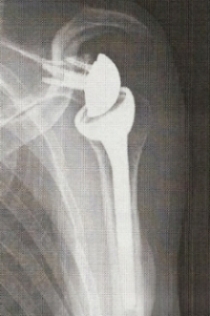

一時修復困難な腱板断裂には、症例により骨頭部を削り腱板を修復するExtra Medialization や反転型人工肩関節置換術(RSA)を行っています。反転型人工肩関節は腱板機能が失われた肩でも肩関節の機能回復が可能です。

a. 解剖型人工関節 b.反転型人工関節